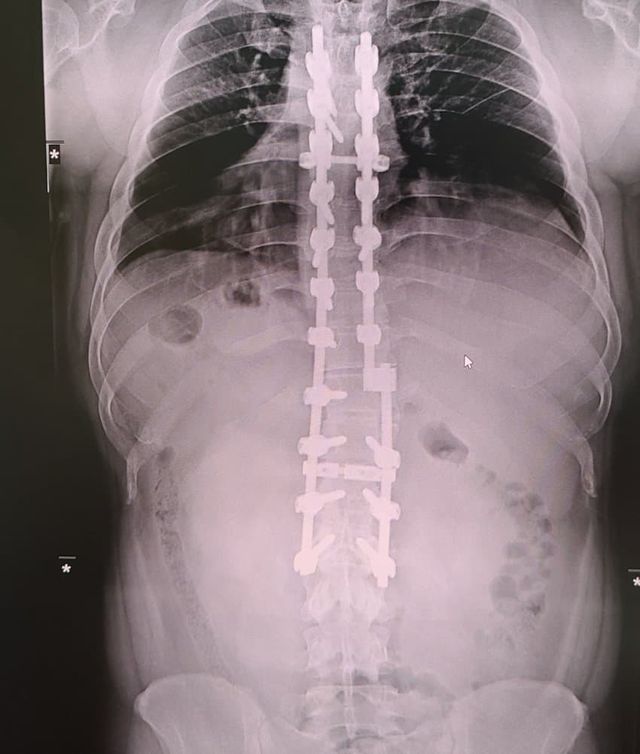

디씨)나 12사에서 죽을뻔하고 척추에 심 21개 박은 사람이다!?

나도 12사때 훈련병시절 완전 군장하고 쓰러지고

척추 무너지고 희귀병 진단받아서

12사 내 의무사단에서 핵고통 받다가 죽다살아난 사람이다